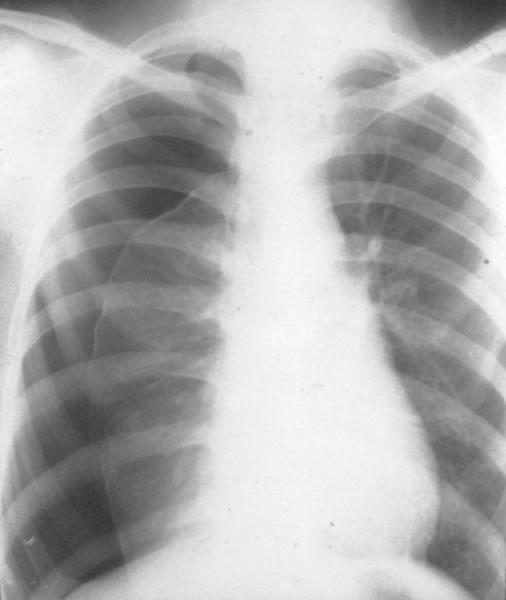

图中是一位右侧气胸患者(图中右面)的电脑断层扫描影像。在胸腔的边缘有着引流管,而图中黑色一片就是邻近于肺膜间(黑)和肋骨(白)的内腔。心脏则在图中央。医学专科胸腔医学、胸腔外科学症状胸痛、呼吸困难、疲劳常见始发于突发性肇因未知、创伤风险因子慢性阻塞性肺病(COPD)、结核病、抽烟诊断方法胸部X光、超声波、电脑断层扫描相似疾病或共病肺部大疱、血胸预防禁烟或戒烟治疗保守治疗、空针穿刺、胸管置放、肋膜黏连术盛行率约每10万人中20例外伤性气胸。

突发一侧胸痛,伴有呼吸困难并有气胸体征,即可作出初步诊断。X线显示气胸征是确诊依据。在无条件或病情危重不允许作X线检查时,可在患侧胸腔积气体征最明确处试穿,抽气测压,若为正压且抽出气体,说明有气胸存在,即应抽出气体以缓解症状,并观察抽气后胸腔内压力的变化以判断气胸类型。在原有严重哮喘或肺气肿基础上并发气胸时,气急、胸闷等症状有时不易觉察,要与原先症状仔细比较。